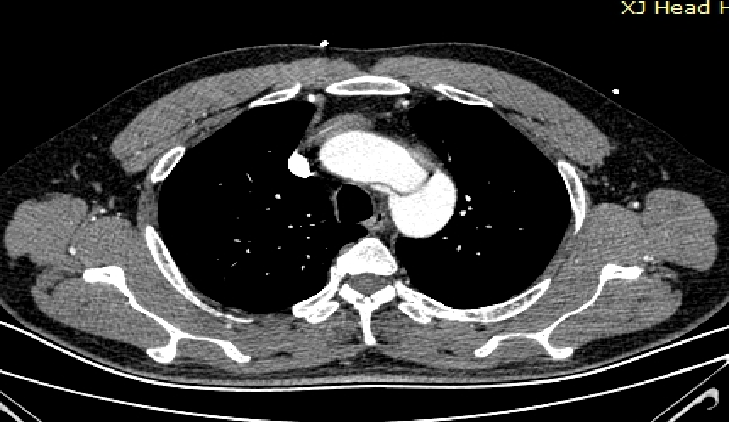

男,49岁,急性AD。2019年1月TEVAR,3月RTAD,行全弓置换+支架象鼻。2022 年1月25日术后复查,结果良好。